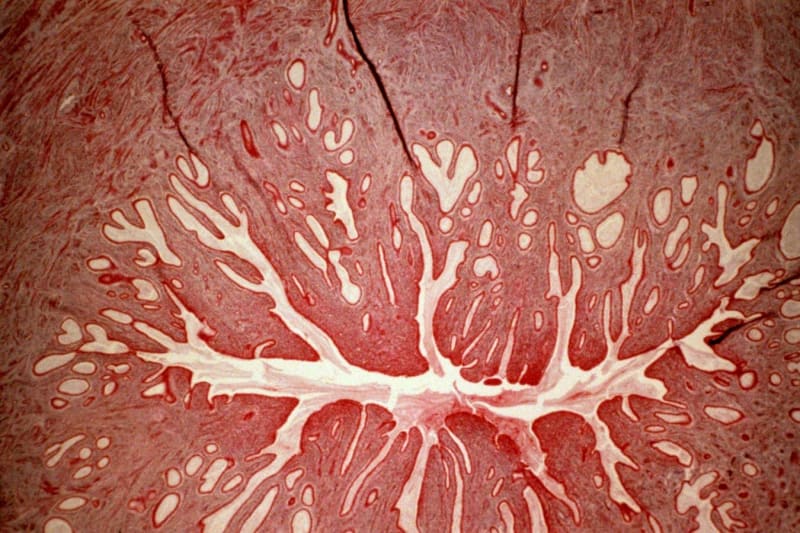

Scientists at the University of California, Davis wondered if adding stem cells could help repair spinal tissue more completely. They created a patch made from stem cells harvested from donated placentas, embedded in a matrix of proteins that help cells grow.

The results exceeded expectations. Brain scans showed the patch completely reversed a dangerous complication where fluid buildup pushes the brain through the base of the skull. All six babies healed perfectly at birth with no abnormal cell growth, a key safety concern when using stem cells in developing fetuses.